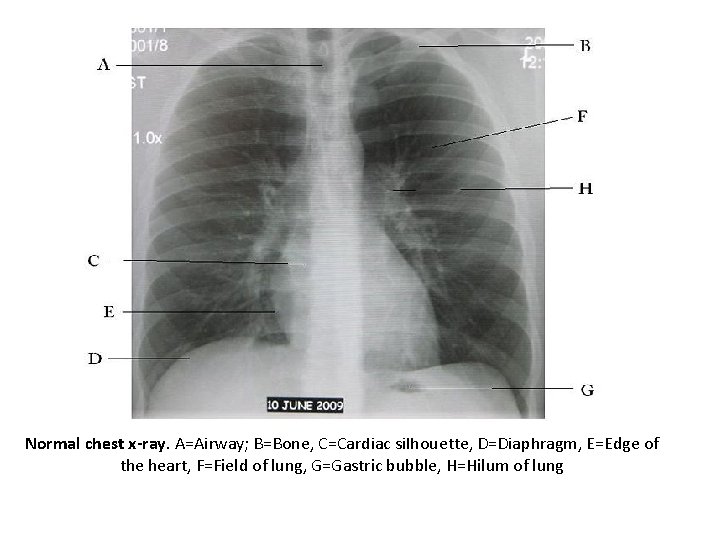

Normal chest x-ray. A=Airway; B=Bone, C=Cardiac silhouette, D=Diaphragm, E=Edge of the heart, F=Field of

Normal chest x-ray. A=Airway; B=Bone, C=Cardiac silhouette, D=Diaphragm, E=Edge of the heart, F=Field of lung, G=Gastric bubble, H=Hilum of lung